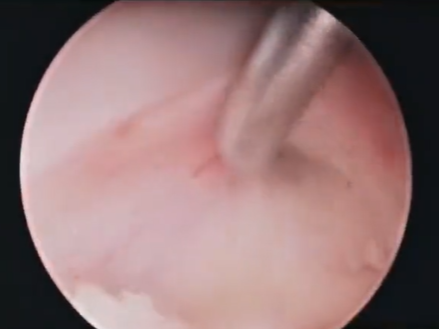

颈前路椎间盘切除植骨融合术(ACDF)是治疗颈椎病的经典手术方式之一,通过神经减压、恢复颈椎的稳定,实现较好的临床疗效。但在实际操作中,空间狭窄、减压区域视野不清、止血困难等因素常导致手术难度增加,且存在病变组织减压不全、神经刺激损伤、食管等重要结构损伤等风险。随着脊柱内镜技术的飞速发展,一些学者将脊柱内镜开创性地与ACDF术式相结合,产生了脊柱内镜辅助ACDF即小切口开放入路(空气/水介质)内镜辅助下ACDF,该技术具有更加清晰和安全的优势,临床疗效令人满意。

镜下放大后能精准地显示致压物及周围解剖关系,处理钩椎关节、椎体后缘唇样增生时,能明确骨赘减压范围,清晰地显露硬膜、神经等重要结构,精准减压、精准止血。

患者取仰卧位,肩部垫高,头自然后仰,顺颈前横纹取颈前横切口,长约3cm,切开皮肤、皮下组织,游离颈阔肌皮瓣,电凝止血,经胸锁乳突肌内侧间隙、颈动脉鞘与气管食管之间的间隙进入椎前,切开椎间筋膜,用定位针标记,C型臂透视定位颈4-5、5-6椎间隙,撑开器撑开颈4-5、5-6椎间隙,生理盐水冲洗下,镜下摘除残留的椎间盘,脊柱内镜探查见左侧椎间盘破裂向后脱出,后纵韧带破裂,一次性无菌磨钻切除椎体后方骨赘及前方椎体,以充分减压,用刮匙去除颈5-6椎间部分软骨板,修整椎间植骨床;清除组织碎片,将自体骨与异体骨混合填充于椎间融合器中,于颈4-5、5-6椎间隙置入Uni-C插片式颈椎自稳定型融合器各1枚,再于颈4-5、5-6椎体前方椎间融合器打入插片各两枚,术中观察及C型臂透视插片及椎间融合器固定良好、位置满意:充分止血,冲洗切口,颈部切口置引流1根,持续负压吸引,逐层缝合,无菌敷料包扎,颈托外固定,术毕。